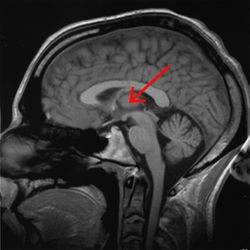

| مقطع صورة رنين مغناطيسي لمخ بشري, المهاد مبين فيه. | ||

المهاد Thalamus (من اليونانية θάλαμος = المهد أو المخدع, غرفة) هو زوج وجزء متماثل في المخ. وتشكل الجزء الرئيسي من diencephalon.